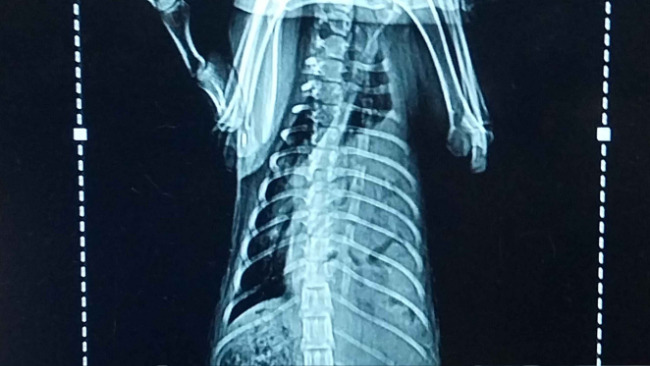

Na nasze nieszczęście po usg i kilku szybkich badaniach zapadła diagnoza- przepuklina przeponowa. Życie może mu uratować tylko operacja.